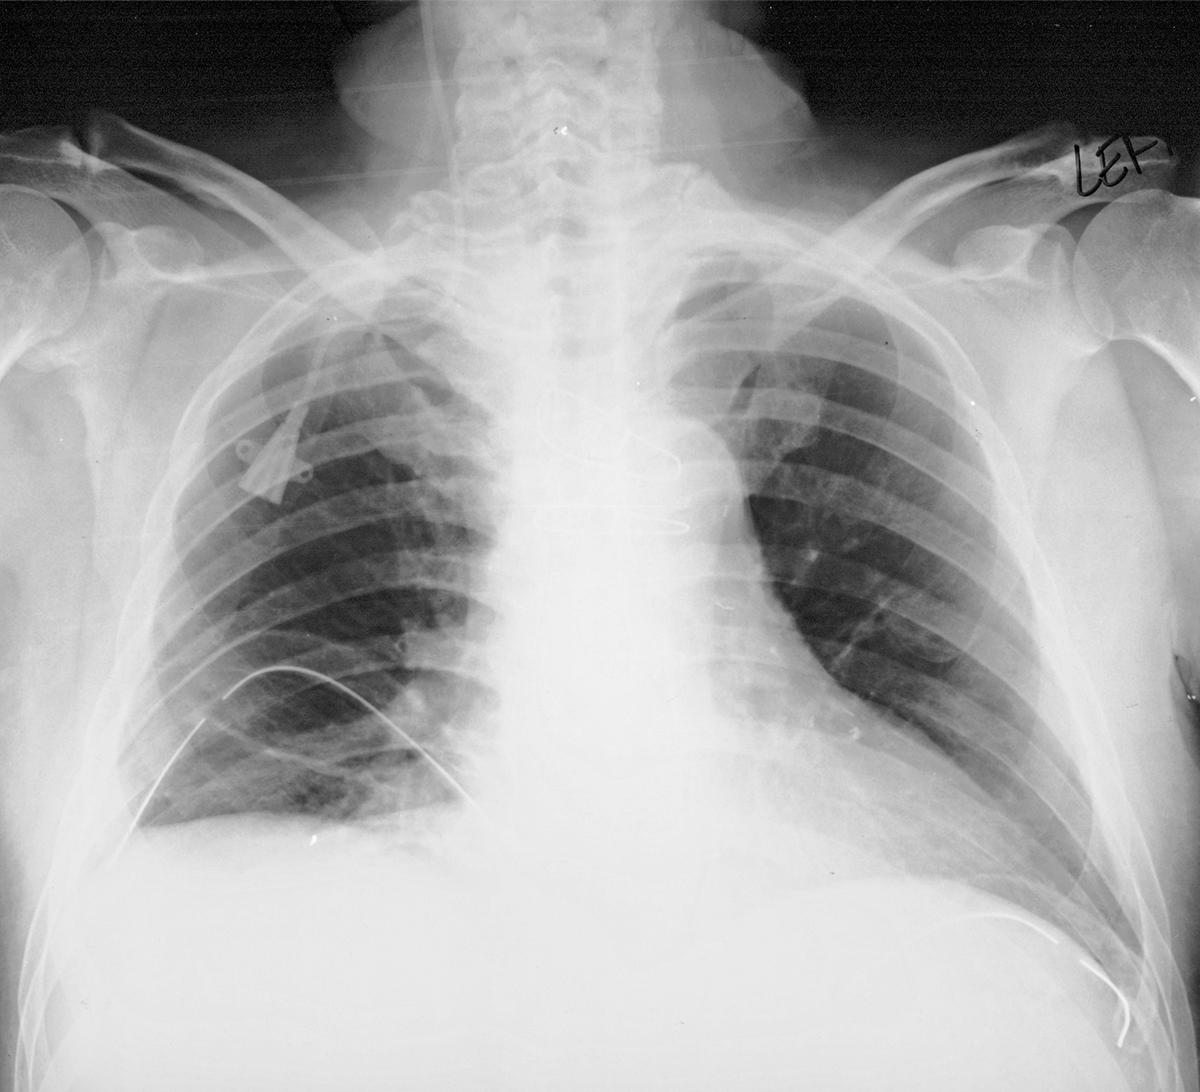

intermediate case of lines and tubes